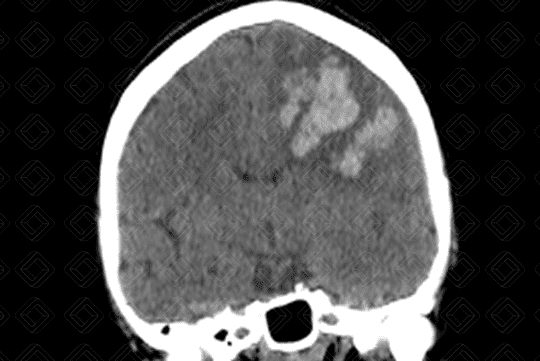

Descrição das imagens: Paciente masculino, 68 anos, com hemorragia intracraniana causada por rotura de um aneurisma da artéria cerebral média esquerda. Observa-se a presença de áreas espontaneamente densas (sangue), intraparenquimatosas, no lobo frontal e parietal esquerdos (setas vermelhas), causando discreto desvio da linha média contralateralmente. Nota-se ainda hipodensidade periférica devendo representar edema.

• Tomografia computadorizada do crânio: Deve ser feita avaliando sua densidade, seu volume, sua localização e sua relação com as estruturas circunjacentes. Lembrar que a densidade compatível com sangue na tomografia computadorizada encontra-se em torno de 50 a 70 UH. Permite ainda avaliar se há efeito compressivo ou desvio de linha média, por exemplo. A aparência da hemorragia intracraniana não complicada na tomografia computadorizada é relativamente direta e de fácil percepção (Figura 1);